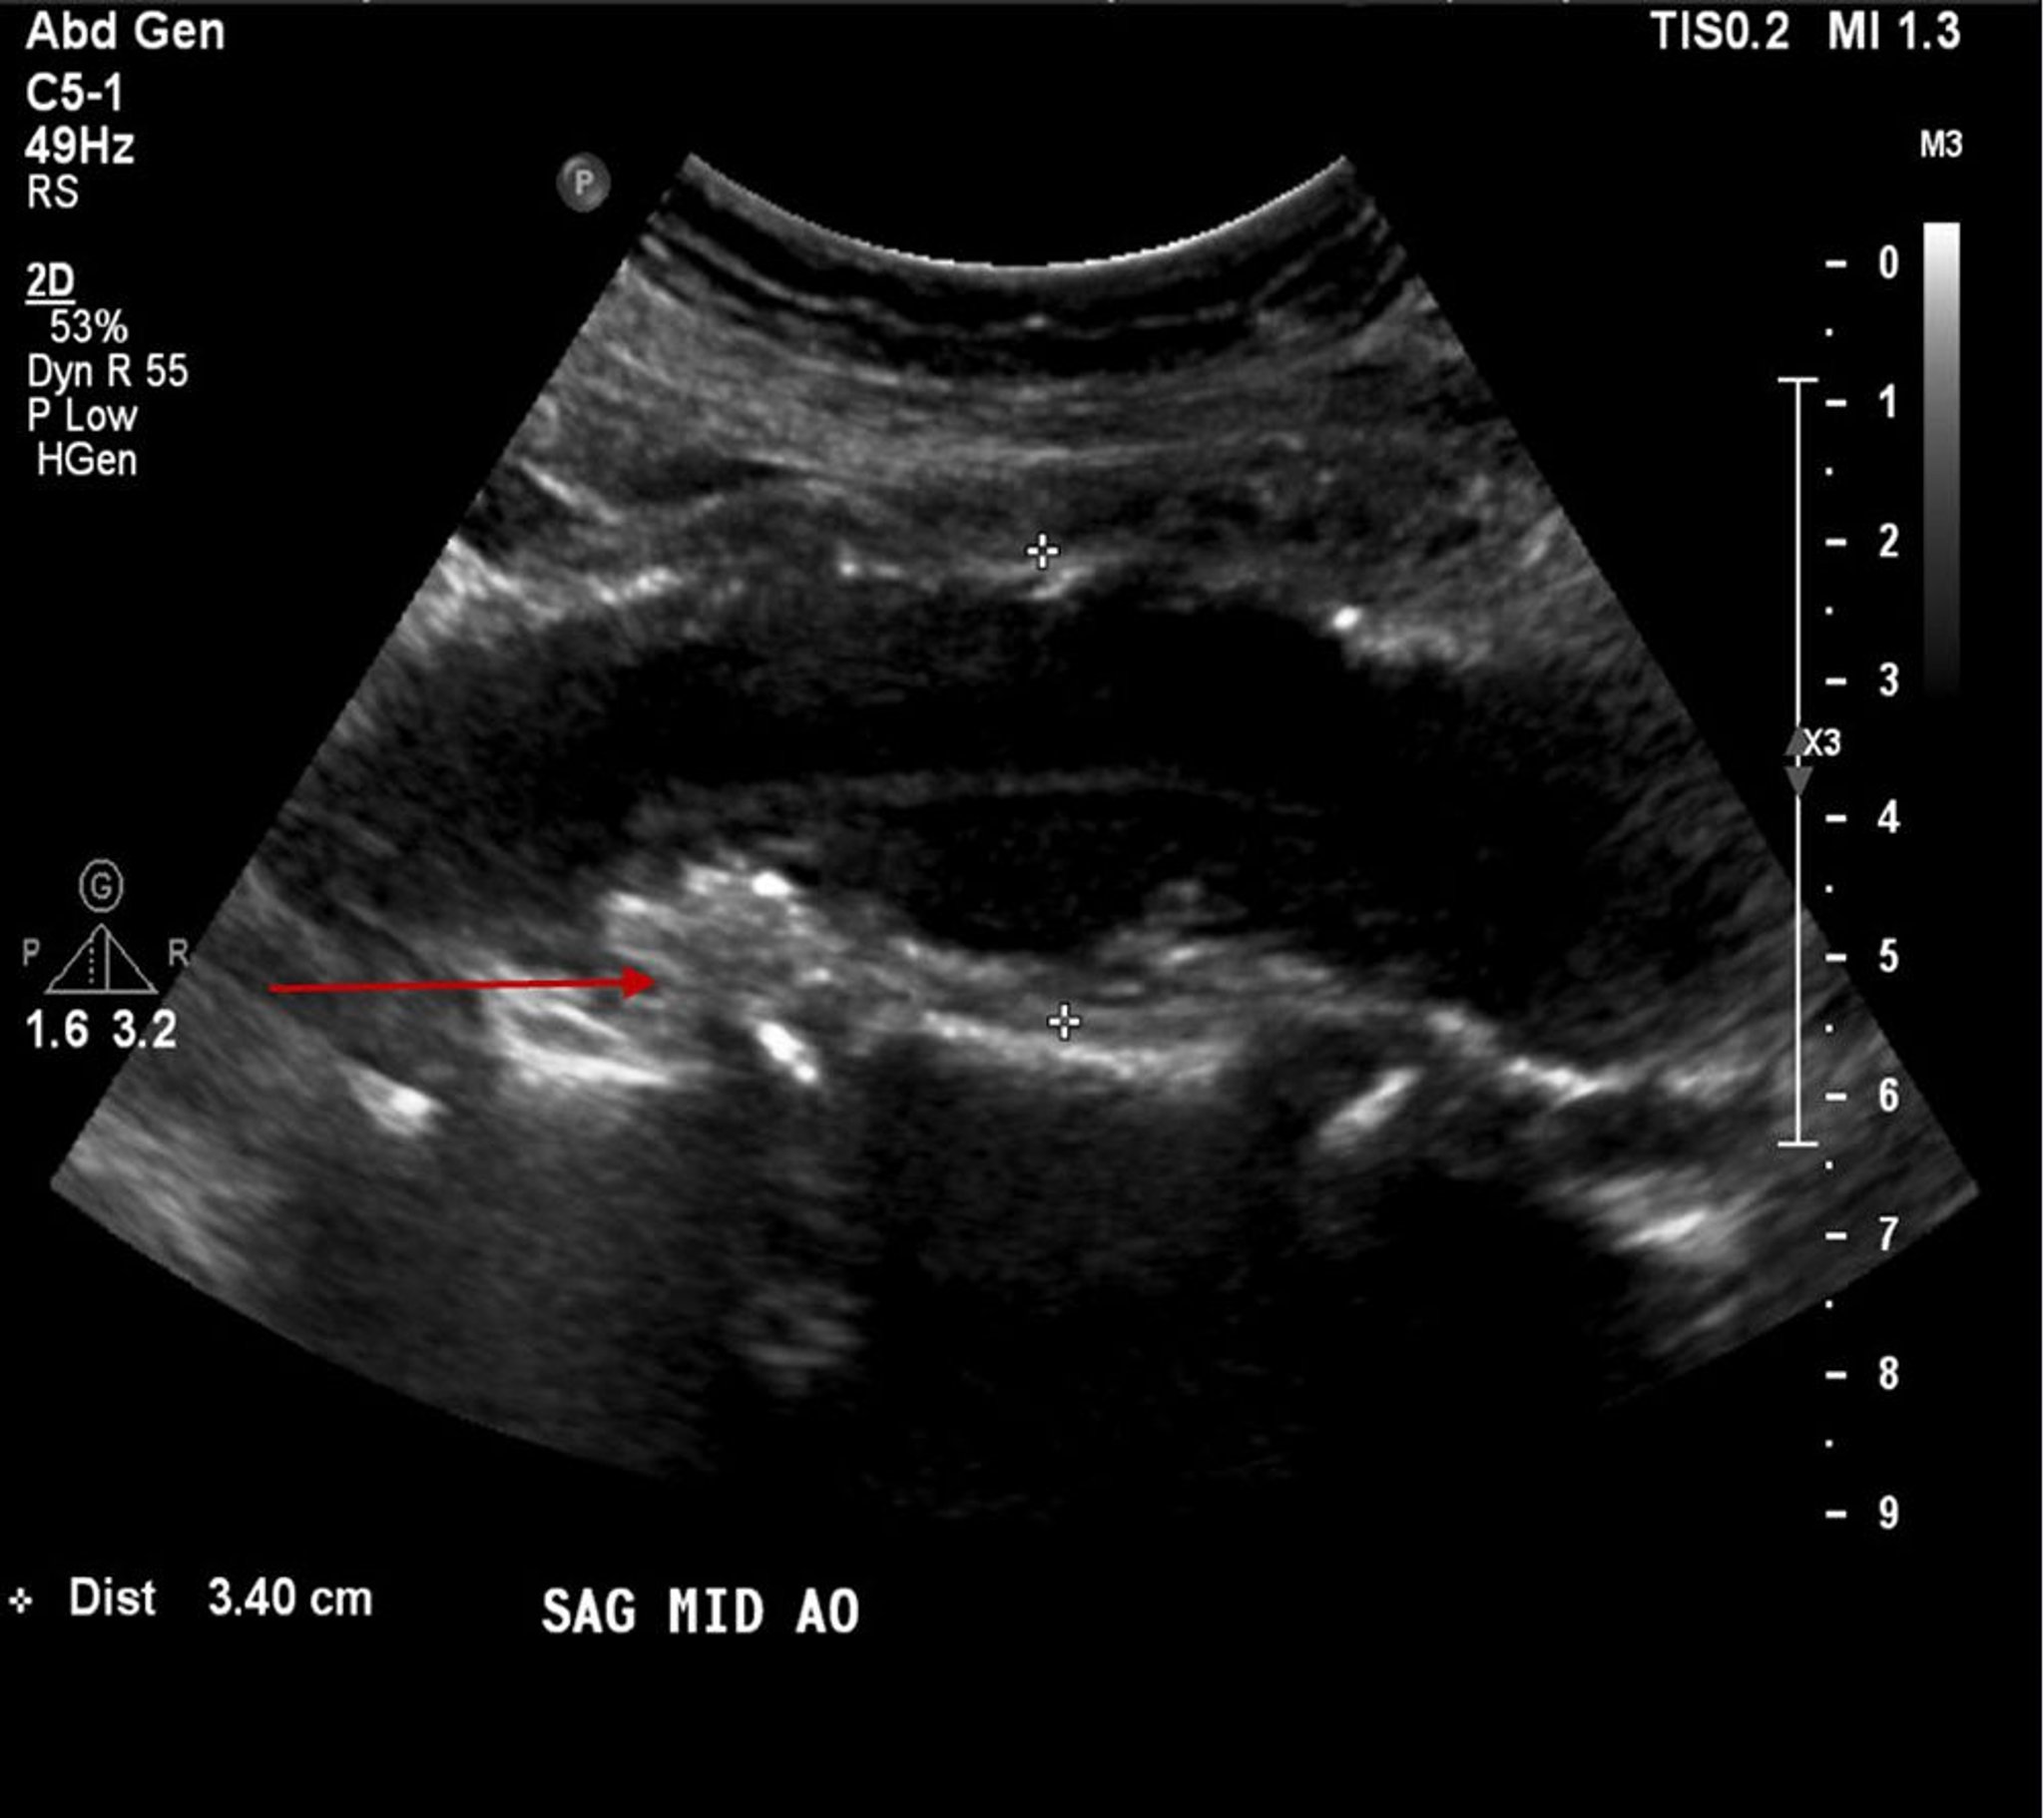

腹部大動脈瘤(超音波画像)

この患者では,3.4cmの腹部大動脈瘤がみられ(白い十字記号の間),アテローム性プラーク,壁在血栓(赤矢印)もみられる。

© 2017 Elliot K.Fishman, MD.